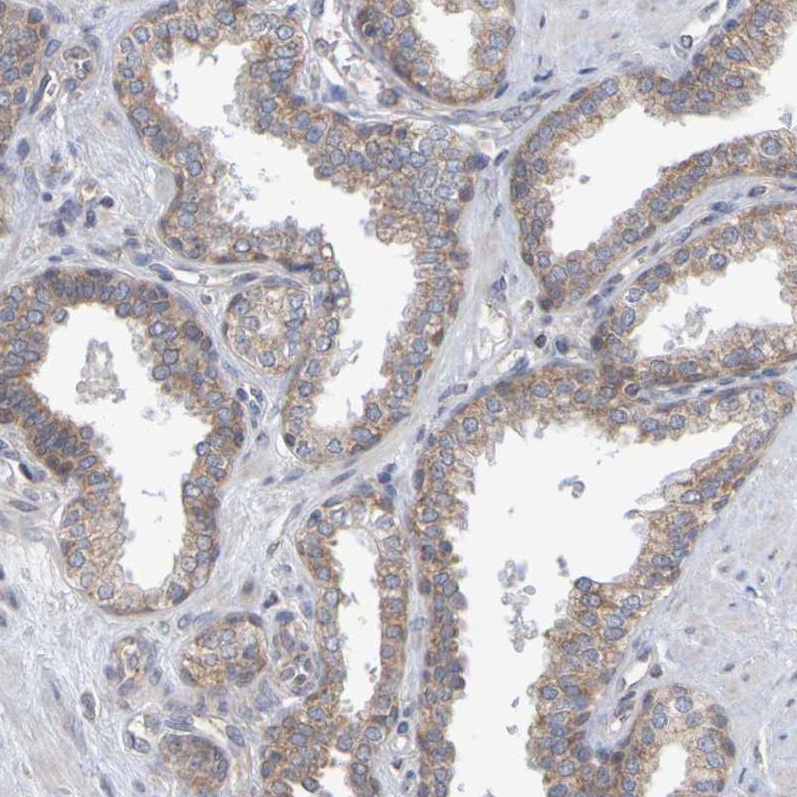

Immunohistochemical staining of human duodenum shows moderate granular cytoplasmic positivity in glandular cells.